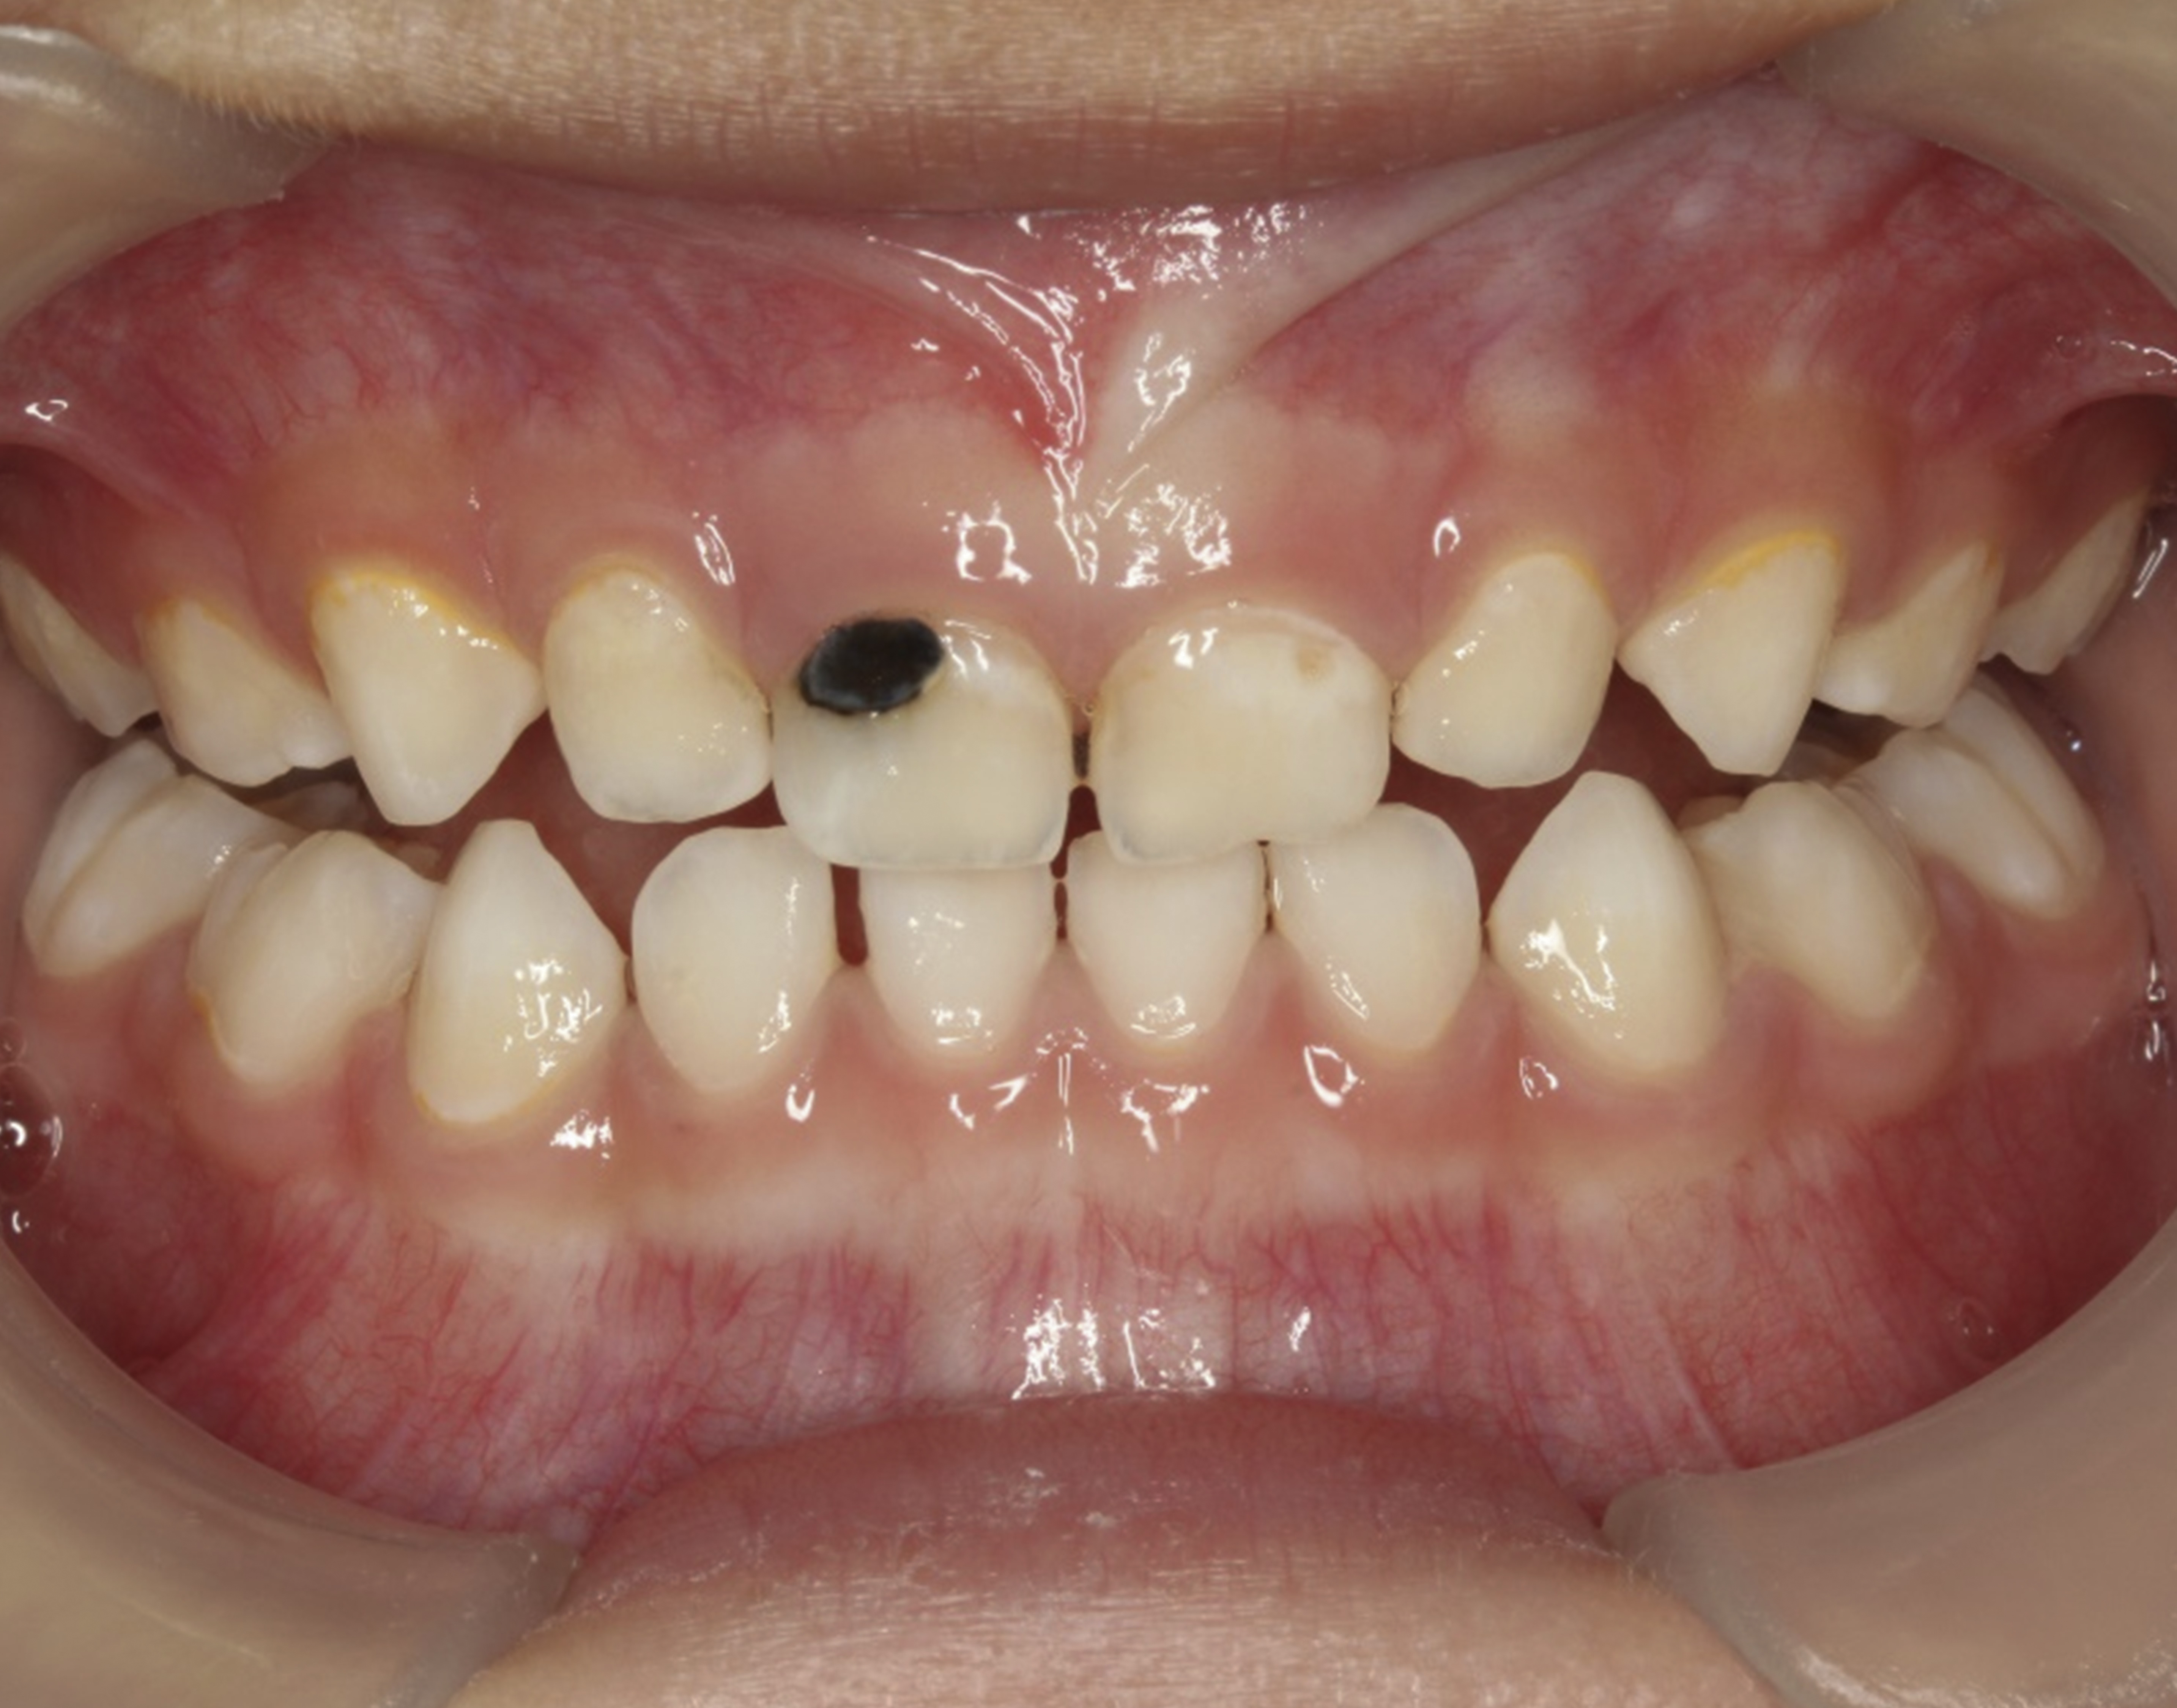

Fig 5. Use of 38% SDF to arrest coronal caries in primary teeth of a young child. The arrested carious lesion had a hard, blackened, and impermeable layer.

Figure 5

The inherent disadvantage of SDF is that the caries lesions will be stained black after SDF application. SDF stops caries progression by forming a hard, blackened, impermeable layer on the tooth surface that is resistant to caries (Figure 5 through Figure 9). The authors’ clinical observations are that the darker the color, the more likely the caries arrested. Some patients may not be pleased with the esthetics of this treatment outcome; therefore, it is important to inform the patients and parents (for child patients) about this treatment outcome. Moreover, SDF can stain clothes and the skin of the body. Though it does not cause any pain or damage, an SDF stain on skin cannot be easily washed away. It takes around 7 days for it to disappear, and the stain on clothes is permanent.22

There is no consensus on the frequency of application, and 38% SDF has been used annually or biannually on clinical trials in children23,31,33,34 and in elderly.30,35 Yee and his co-worker found one-off application of 12% SDF was ineffective in arresting caries in children.31 The present authors applied 38% SDF weekly for 3 weeks to speed up the process of caries arrest and for treatment of rampant caries.36 One of the present authors’ case reports demonstrated that three weekly applications of 38% SDF can arrest rampant caries and relieve pain from hypersensitivity on a teenager. The SDF-treated caries were found arrested, and they turned coal black in appearance (Figure 9).